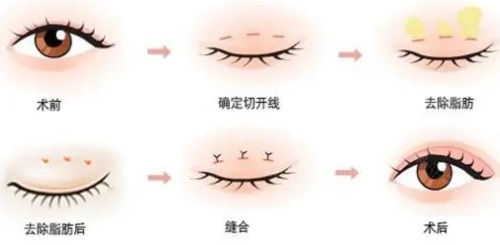

手术方式多样

他熟悉全切、埋线等各类手术操作方式。对于眼皮薄、皮肤紧致的年轻人,他会推荐埋线双眼皮,这种方式改善快,几乎无疤痕,若不喜欢还可随时拆掉;而对于眼皮松弛、肿眼泡等情况,他会采用全切双眼皮,能有效去除多余的皮肤和脂肪,结果持久。